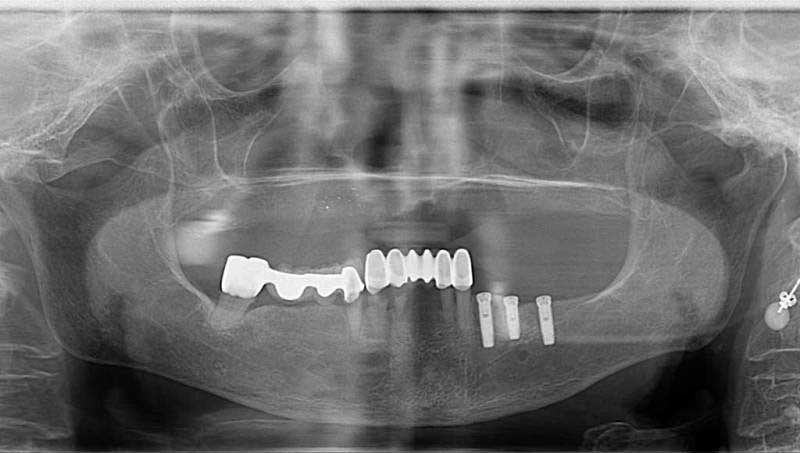

案例2